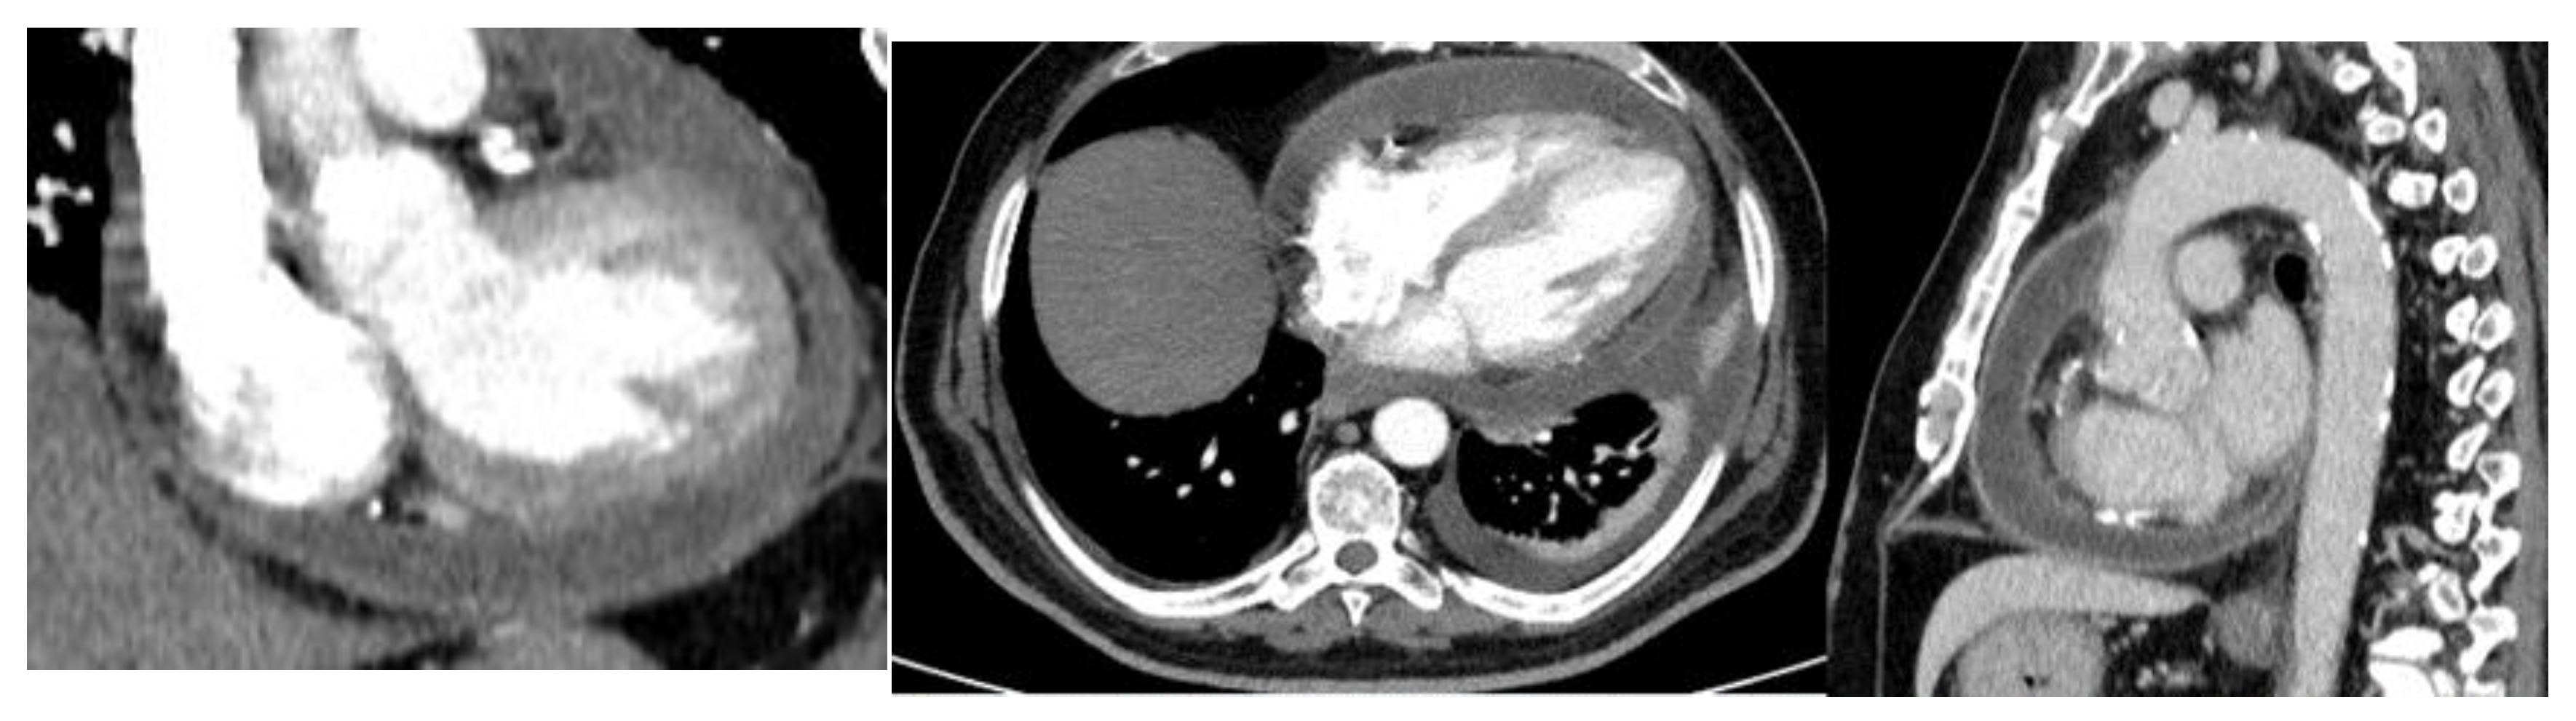

Total-body contrast-enhanced computed tomography (CT) was performed, which showed large pericardial effusion with hyperemia of the pericardial layers, associated with moderate bilateral pleural effusion, more significant on the left side (Figure 2).

Figure 2. Contrast enhanced in thoracic CT. Severe pericardial effusion and left pleural effusion were observed.